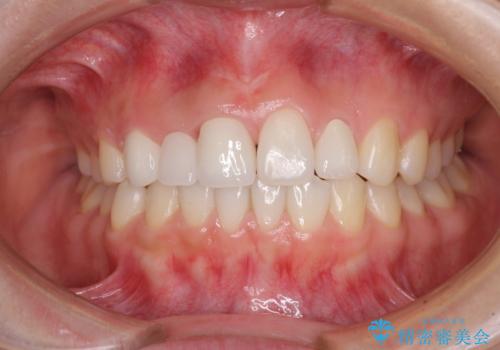

前歯を整えたい 小さい前歯がある 矯正・セラミック併用で美しく インビザラインでも抜歯矯正できます

総合歯科治療 矯正治療と失活歯のセラミック補綴治療

欠損歯と矮小歯 矯正治療と前歯のセラミック治療